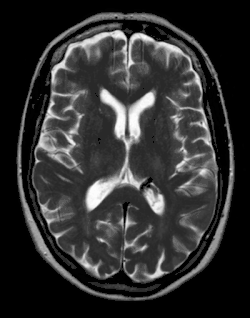

- Venöse Malformationen (VM): Die VM ist die häufigste Form einer Gefäßmalformation. Sie hat im Gegensatz zu den AV-Malformationen stets nur einen geringen Blutfluss. Es handelt sich um abnorm geformte und erweiterte Venen. Die Wand dieses Kanalsystems ist aufgrund eines Mangels an glatten Muskelzellen ungewöhnlich dünn, sie sind jedoch von Endothel ausgekleidet. Sie sind livid-blaue, blutgefüllt und zwischen den Gefäßräumen befindet sich kein Parenchym. Häufig befinden sich Thromben innerhalb des Kavernoms.